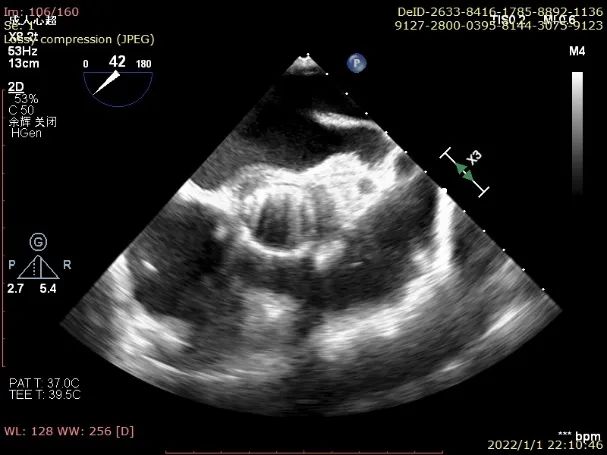

1. 升主动脉扩张,主动脉窦部内径4.3cm,窦管交界近消失,内径5.1cm,主动脉瓣三瓣瓣缘回声钙化、粘连,开放不佳,CW:收缩期主动脉瓣口最大血流速度:3.1cm/s,最大压差:38mmHg,平均压差:19mmHg,主动脉瓣环径2.7cm,主动脉瓣弓部内径3.5cm。肺动脉增宽。肺动脉瓣形态、活动正常;

6. CDFI:主动脉半口舒张期可见大量反流信号。

超声提示:

升主动脉扩张;

主动脉瓣钙化、轻度狭窄并重度关闭不全;

TEE示主动脉瓣大量反流